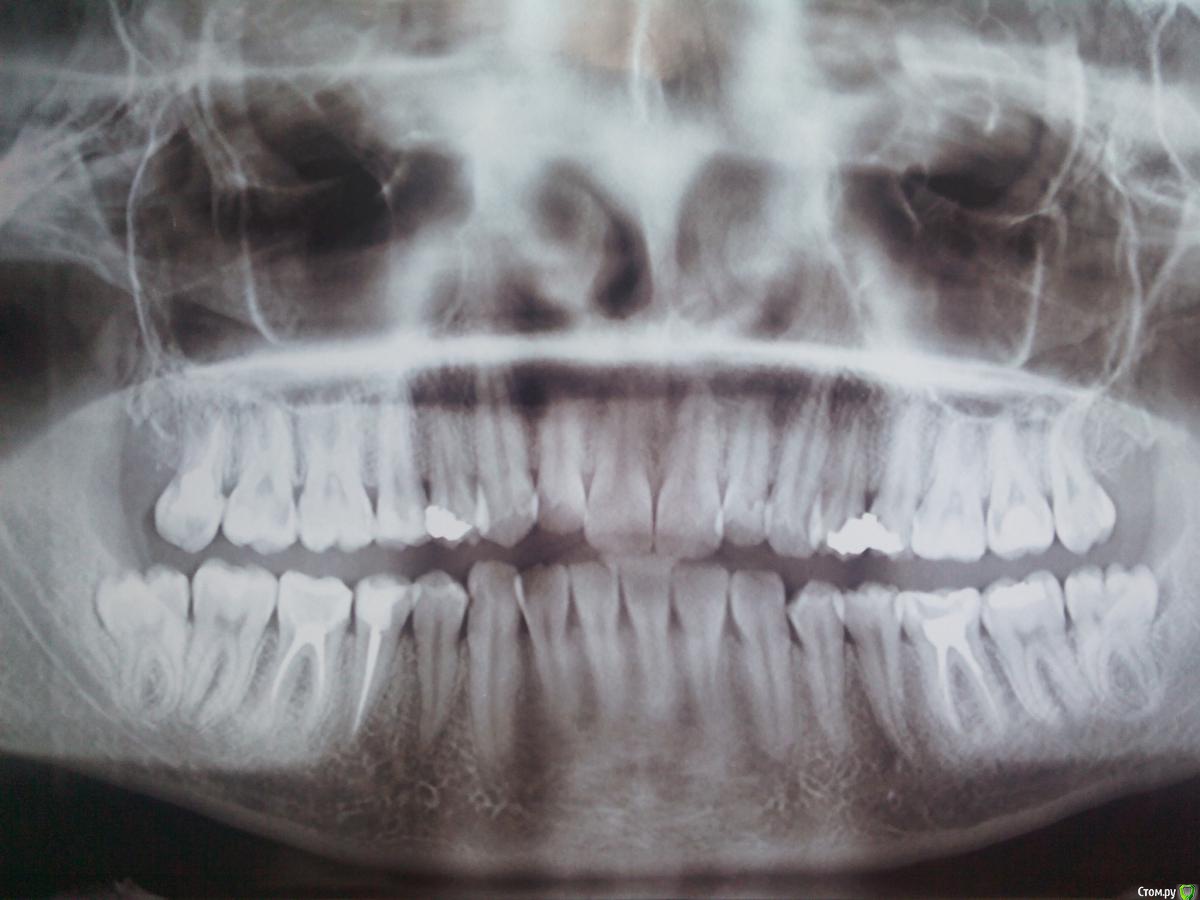

Рыжъ Опубликовано 12 мая, 2015 Поделиться Опубликовано 12 мая, 2015 (изменено) Здравствуйте, уважаемые доктора! Ж, 28 лет. Нижняя правая восьмерка не прорезалась до конца, из-под десны кокетливо выглядывает один ее кончик. Проблем не доставляла никогда, не болела, другая нижняя восьмерка в зубном ряду ровненько стоит. Три дня назад появились спонтанно боли на термические раздражители, на горячее и холодное. Болит после раздражителя примерно час еще. Боль сильная, ноющая. Не пульсирует. Десна розовая, не увеличена, нигде нет припухлостей. Но боли адские. Ночью болит сама по себе. Я очень мучаюсь. Сделала рентген, снимки прилагаю. Подскажите, какова моя тактика? Удалять восьмерку или нет? Можно ли сохранить зуб в таком вот состоянии? Не опасно ли это для семерки? Почему пульпитные боли начались, неужели из-за нехватки места для восьмерки? Изменено 12 мая, 2015 пользователем Рыжъ Ссылка на комментарий

Bier Опубликовано 12 мая, 2015 Поделиться Опубликовано 12 мая, 2015 пульпитные боли потому что где-то пульпит. Проверьте верхний 7й.Верхний 8й - удаляйте. Ссылка на комментарий

annda Опубликовано 12 мая, 2015 Поделиться Опубликовано 12 мая, 2015 А на верхнем 7м что за дефект чернеется вплотную к 6ке?Тут снимок в прикусе будет самым точным,но и прицельный можете показать. Ссылка на комментарий

red_butler Опубликовано 13 мая, 2015 Поделиться Опубликовано 13 мая, 2015 нужно искать пульпит, внимательно посмотреть 1.7 1.4 4.3 и 4.7 1 Ссылка на комментарий

Bier Опубликовано 14 мая, 2015 Поделиться Опубликовано 14 мая, 2015 по вашему снимку очень смущает верхняя 7ка (17й) Ссылка на комментарий